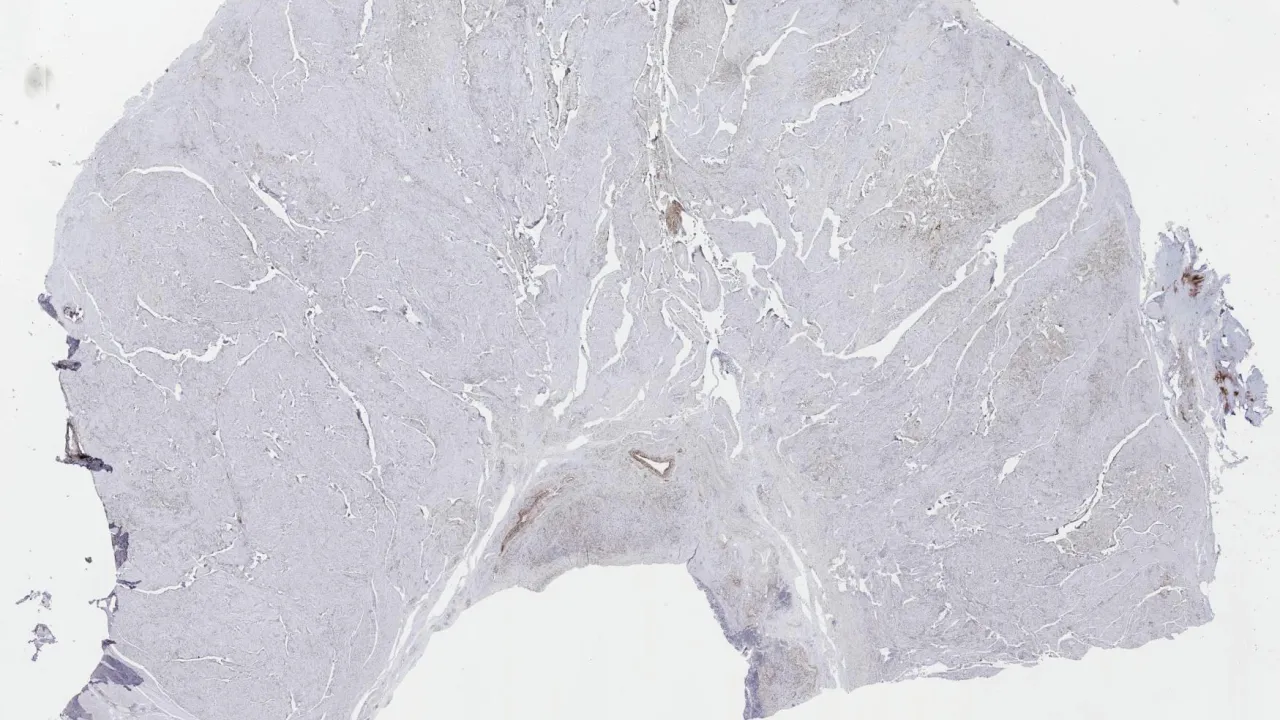

Lymph Node, Nodular lymphocyte predominant Hodgkin lymphoma, CD3 stain